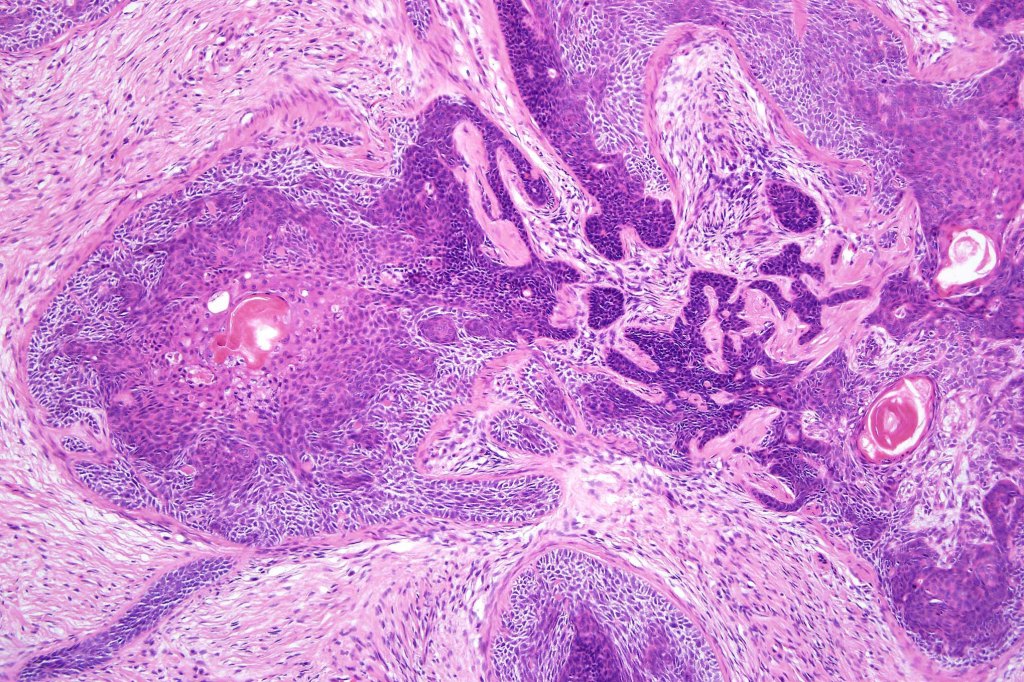

•Variable keratocysts

•A rich fibromyxoid mesenchymal stroma with variable papillary mesenchymal bodies (sometimes these are absent)

•Trichogerminoma is a distinctive variant being composed of tumor nodules with basaloid cells surrounding pale or eosinophilic micronodules (Zellballen)

•Panfolliculoma represents an often-cystic trichoblastoma showing differentiation toward all follicular elements